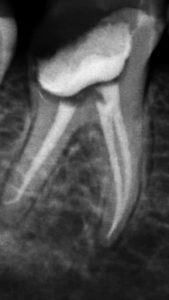

El sistema radiográfico digital New IDA cuenta con un sensor que usa las tecnologías asociadas del CMOS (Complementary Metal-Oxide-Semiconductor), fibra óptica protectora y centelleada. Ese sensor fue fabricado para adquirir la imagen de rayos x digital de alta calidad de la arcada humana y sus estructuras.El proceso de adquisición es realizada posicionado el sensor en la parte interna de la boca atrás de la estructura que se desea realizar el examen.

La estructura debe ser expuesta a una dosis de rayos x usando una fuente externa. Una vez expuesto, el sensor realiza una conversión de los fotones de rayos x en una señal digital y enseguida transfiere para una computadora vía conexión USB (Universal Serial Bus). El software de gestión de imagen dental realiza el interfaz con el sistema New IDA y el usuario, podrá visualizar, mejorar, almacenar, enviar, imprimir entre otras funciones

Es el sensor digital intraoral de DabiAtlante que ofrece imágenes de solución eficiente para obtener un diagnóstico más claro, preciso y avanzado.

Captura imágenes de alta definición en tiempo real.